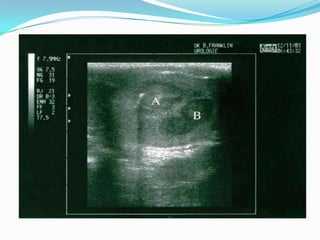

Scrotal ultrasound

 Ultrasonography of the scrotum is a rapid, reliable

technique to exclude hydrocele or epididymitis.

 Ultrasonography of the scrotum is basically an

extension of the physical examination.

 Hypoechoic area within the tunica albuginea is

markedly suspicious for testicular cancer.